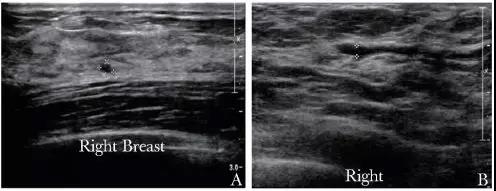

乳头溢液是乳腺疾病的常见症状,其发病率仅次于乳房肿块及乳房疼痛,占门诊患者主诉症状的4.8%~7.4%[1]。 乳头溢液又分为生理性和病理性两种。病理性乳头溢液的病因包括导管内乳头状瘤、乳腺腺病、导管扩张、乳腺癌等[2]。其中,导管内病变是造成乳头溢液的主要病因,溢液性状可分为血性和非血性,后者又包括浆液性、混浊黏液样等。 本文通过回顾性分析173例病理性乳头溢液患者的临床、病理特点及其诊治情况,以期发现病理性乳头溢液,特别是血性溢液是否存在特殊的临床病理特点,临床诊断方法能否为治疗提供充分依据,治疗及术后随访是否合理,从而为该病临床诊治提供依据。 1 资料与方法 1.1 临床资料 回顾性收集北京协和医院2015年1月至12月间住院并手术的病理性乳头溢液(血性溢液、黄色浆液性或混浊黏液样溢液)患者的临床、病理以及术后随访资料。 纳入标准: (1)非妊娠期、非哺乳期女性; (2)首发症状为自发性乳头溢液; (3)乳头溢液为血性溢液、黄色浆液性或混浊黏液样溢液; (4)术前体格检查,乳腺超声、钼靶等影像学检查,术后石蜡病理等资料齐全。 排除标准: (1)男性; (2)首发症状为乳房肿物; (3)乳汁样或无色透明样乳头溢液; (4)术前评估不完善; (5)于外院行手术治疗。 1.2 术前检查 所有患者术前均进行体格、超声及钼靶检查。体格检查主要记录乳头溢液单侧、双侧、单孔或多孔及是否合并可触及肿块。超声检查均于我院超声科进行,采用PHILIPS HD11XE超声机,探头采用L12-5,频率为5~12 MHz。患者仰卧位接受检查,主要记录乳房内是否存在低回声病变或导管内低/高回声。乳腺钼靶检查均于我院放射科进行,患者取立位,行常规乳腺头尾位及内外侧斜位检查。根据美国放射学乳腺影像报告和资料系统(BI-RADS)进行诊断,主要记录是否存在钙化及肿块。 1.3 手术方式 所有患者术中先采用美兰进行切口定位(图1A),然后行乳腺病变导管及相关腺叶切除术(图1B)。术中冰冻或石蜡病理结果回报为恶性病变的患者,进一步行保乳手术或乳房切除术,腋窝行前哨淋巴结切除术或腋窝淋巴结清扫术。 图1 乳腺病变导管及相关腺叶切除术 A.手术切口;B.切除的病变标本 1.4 病理检测 术后病理均采用HE染色。HE染色石蜡病理切片均由病理科医师根据2012版世界卫生组织乳腺肿瘤诊断标准进行诊断[3]。 1.5 术后其他治疗及随访 术后根据手术方式及病理结果,部分患者行化疗、放疗及内分泌治疗,所有患者均未行曲妥珠单克隆抗体靶向治疗。所有患者均采用电话随访方式进行术后随访。 1.6 统计学处理 采用SPSS 22.0统计学软件进行统计分析,符合正态分布的计量资料采用均数±标准差表示,非正态分布的计量资料以中位数(四分位数)表示,组间比较采用t检验或Mann-Whitney U检验;计数资料采用频数(率)表示,组间比较采用χ2检验或Fisher精确概率检验。以P<0.05为差异具有统计学意义。 2 结果 2.1 一般临床资料 共173例符合纳入和排除标准的患者入选本研究,均为女性,平均年龄(45.65±13.48)岁,中位病程3(1, 12)个月。其中血性溢液119例(68.8%,119/173),非血性浆液性溢液54例(31.2%,54/173);仅2例(1.2%,2/173)为多孔溢液,其余均为单孔溢液;168例(97.1%,168/173)为单侧乳头溢液,5例(2.9%,5/173)为双侧乳头溢液。 173例患者中,23例术前触诊可触及乳腺肿块,150例未及乳腺肿块;超声检查发现111例(64.2%,111/173)患者显示乳房低回声或导管内低/高回声(图2),62例未见异常;钼靶检查中,仅35例患者发现乳腺肿块影或钙化灶(图3),138例患者钼靶无异常。 图2 乳腺超声提示乳房内低回声(A)及导管扩张(B) 图3 乳腺钼靶提示合并钙化及肿块 A、C. 乳腺头尾位;B、D. 乳腺内外侧斜位 173例患者中,160例先行乳腺病变导管及相关腺叶切除,9例患者行乳腺肿物切除术+病变导管及相关腺叶切除术,4例患者仅行乳腺肿物切除术。根据术中冰冻或石蜡结果,27例患者诊断为乳腺癌,其中4例行包括乳头乳晕的中心象限局部扩大切除术,3例行中心象限局部扩大切除术+前哨淋巴结活检术,14例行乳腺单纯切除+前哨淋巴结活检术,1例仅行乳腺单纯切除术,5例行乳腺改良根治术。 术后石蜡病理回报:乳腺癌27例,其中浸润性癌6例,导管内癌19例,其他类型癌(黏液癌及神经内分泌癌)2例,行前哨淋巴结活检或腋窝淋巴结清扫术的患者,术后病理均未见淋巴结转移;不典型增生15例;良性病变以导管内乳头状瘤为主,共92例;其他良性病变包括乳腺腺病21例、纤维腺瘤4例、导管扩张14例(图4)。 图4 乳头溢液患者术后病理切片(HE,×100倍) A.乳腺导管扩张及导管内乳头状瘤;B.乳腺导管内乳头状癌;C.乳腺浸润性导管癌;D.特殊类型乳腺癌(黏液癌) 术后共23例患者接受内分泌治疗,12例应用三苯氧胺类药物,11例应用芳香化酶抑制剂类药物。4例患者术后行放疗,1例因乳头血性溢液伴多发肿块且年龄小于30岁,术后予含蒽环类及紫衫药物方案化疗,均未行靶向治疗。 2.2 亚组分析 2.2.1 血性溢液和非血性溢液患者的临床、病理特点比较 两组患者在年龄、病程、术前体格和钼靶检查结果、术后病理分型等方面差异无统计学意义(P均>0.05);在术前超声检查(是否发现病变)及术后病理诊断(是否为乳腺癌)方面差异存在统计学意义(P=0.012和P=0.045)(表1)。 表1 血性溢液和非血性溢液患者临床/病理特点比较 2.2.2 血性溢液患者中良恶性病变的临床特点比较 在血性溢液患者中,除乳腺癌组患者年龄显著高于良性病变组(P=0.014)外,两组其他临床特征差异均无统计学意义(P均>0.05)(表2)。 表2 血性溢液患者中良恶性病变组临床资料比较 2.3 随访情况 患者术后中位随访17(14,20)个月。病理诊断为乳腺癌者均无复发转移或死亡。病理诊断为良性病变者中,5例术后出现新发乳腺肿物,表现为超声可见乳腺内低回声结节,均予继续随访观察;1例术后出现该侧乳房的炎性病变,予手术切除;1例术后5个月出现对侧乳头非血性溢液,予手术治疗。 3 讨论 病理性乳头溢液常常提示乳腺疾病,特别是乳腺恶性疾病的发病风险升高。本研究中,乳腺癌及不典型增生占病理性乳头溢液的24.28%,导管内乳头状瘤占病理性乳头溢液的53.18%。与文献报道基本一致[4]。故临床上,一旦患者出现病理性溢液症状,包括血性溢液、黄色浆液性溢液或混浊黏液样溢液等,需提高警惕,及时手术治疗。 Zervoudis等[5]报道,由乳腺病变导致的病理性乳头溢液多为单孔单侧。本研究中,病理性乳头溢液中171例为单孔溢液,仅2例为多孔溢液;168例为单侧乳头溢液,5例为双侧乳头溢液,与文献报道一致。但在血性/非血性溢液组,血性溢液的良/恶性病变组中,病变是否单孔、单侧并无明显差异,可能与多发多孔乳头溢液多考虑为良性病变,未收治手术,导致多孔及双侧乳头溢液患者样本量较少有关。 多数学者认为血性溢液是乳腺癌相关的高危因素之一。Chen等[4]通过Meta分析得出结论,血性溢液患者患乳腺癌的风险较其他性状溢液患者高。王富文等[6]的研究认为,血性溢液组癌前病变/恶性率明显高于非血性溢液组。但也有部分学者认为两者之间并无绝对对应关系。Morrogh等[7]报道,血性溢液并不预示着恶性病变或高危风险,而非血性溢液亦不能排除恶性肿瘤的可能。 本研究中,血性溢液中乳腺癌的发病率与非血性溢液中乳腺癌的发病率存在显著差异,血性溢液提示乳腺癌的高风险。但在非血性溢液组,乳腺癌的发病率为7.4%,不典型增生为7.4%。故在出现非血性病理性溢液时,亦不可放松警惕。从病理类型看,非血性溢液组乳腺癌均为导管内癌,而血性溢液组则有近1/3为浸润性癌。本研究认为血性溢液更值得临床上予以重视。 临床检查方面,Lippa等[8]报道,“可疑”的病理性溢液如血性溢液比“良性”病理性溢液有更多的临床检查及影像学发现。本研究中,血性溢液组合并更多超声检查阳性所见,与非血性溢液组存在显著差异,与文献报道一致。而临床体格检查是否合并肿块和钼靶检查则并未表现出差异,可能与亚洲女性乳房较致密,钼靶发现病灶困难等有关。在血性溢液的良恶性病变中,3种检查均无明显差异。故是否合并肿块及超声、钼靶检查在血性溢液是否为恶性病变的鉴别诊断中,无法提供有效的临床证据,与文献报道[9-10]基本一致。 由于超声和钼靶诊断乳头溢液敏感度低,传统的导管碘油造影及溢液涂片误诊率高。 Teboul[11]在20世纪90年代首先应用乳管镜检查,试图解决乳头溢液病因诊断及病变定位这两个难题。但由于导管内病变以多发病变最为常见,乳管镜检查通常只检查1~2个导管,故无法了解乳腺的整体情况;其次,乳腺癌大多起源于终末导管,乳管镜检查到达较困难;再次,乳管镜检查仅从形态学进行诊断,准确率低,如取活检组织进行病理检查,往往病理标本量少,无法进行有效评估[12]。 徐海滨等[13]在血性乳头溢液的患者中进行乳管镜检查,对恶性病变的检出率仅为53.3%。 华盛顿大学医学院对2006至2010年的121例乳头溢液患者进行乳管镜检查,检查结果阴性的患者中,仍有44%的患者检出乳腺导管内癌或浸润性癌[14]。因此对乳管镜检查的阴性结果不应放松警惕。 此外,乳管镜检查常会造成乳腺导管壁的损伤,乳头溢液停止,这样反而会掩盖病情[15]。乳管镜检查亦无法为乳头溢液的诊断提供有效证据。 血性溢液良恶性病变两组中,年龄存在显著差异,年龄较大者出现血性溢液较年轻患者更提示恶性病变可能[(54.04±18.57)岁比(43.64±12.56)岁,P=0.014],这与乳腺癌发病高峰值基本一致[16]。 本研究中,术后病理恶性者多为导管内癌,仅有0.03%为浸润性癌,均未见腋窝淋巴结转移。术后随访未见恶性病变复发及转移,良性病变患者中仅有1例出现炎症病变并行手术治疗,余术后随访出现乳腺结节均考虑良性病变可能性大,继续予以观察。 综上,本研究认为血性溢液提示高乳腺恶性病变风险,年龄较大者则风险更高。但非血性病理性溢液亦不容忽视。大部分患者术前超声检查均有阳性发现,血性溢液者更甚,但术前体格、超声及钼靶检查并不能为良恶性病变的鉴别提供有效依据。及时手术治疗是明确诊断同时达到治疗目的的重要手段,且及时进行手术治疗的乳头溢液患者术后预后较好。 参考文献 [1]Tang SS,Twelves DJ,Isacke CM,et al.Mammary ductoscopy in the current management of breast disease[J].Surg Endosc,2011,25:1712-1722. [2]Park CJ, Kim EK, Moon HJ,et al.Reliability of breast ultrasound BI-RADS final assessment in mammographically negative patients with nipple discharge and radiologic predictors of malignancy[J].J Breast Cancer, 2016,19:308-315. [3]Lakhani SR,Ellis IO,Schnitt SJ,et al.WHO classification of tumours of the breast. World Health Organization classification of tumours [M].4th ed.Lyon:IARC Press,2012. [4]Chen L,Zhou WB,Zhao Y,et al.Bloody nipple discharge is a predictor of breast cancer risk:a meta-analysis[J].Breast Cancer Res Treat,2012,132:9-14. [5]Zervoudis S, Iatrakis G, Economides P, et al. Nipple discharge screening[J]. Womens Health(Lond Engl), 2010, 6:135-151. [6]王富文,林燕苹,何萍青.106例病理性乳头溢液(PND)临床分析[J].复旦学报,2013, 40:714-717. [7]Morrogh M, Park A, Elkin EB, et al. Lessons learned from 416 cases of nipple discharge of the breast[J]. Am J Surg, 2010, 200:73-80. [8]Lippa N,Hurtevent-Labrot G,Ferron S,et al.Nipple discharge:The role of imaging[J].Diagn Interv Imaging,2015,96:1017-1032. [9]Ouldamer L,Kellal I,Legendre G,et al.Management of breast nipple discharge[J].J Gynecol Obstet Blol Reprod,2015,44:927-937. [10]Sabel MS.Helvie MA,Breslin T,et al.Is duct excision still necessary for all cases of suspicious nipple discharge? [J].Breast J,2013,18:157-162. [11]Teboul M.A new concept in breast investigation:echo-histological acino-ductal analysis or analytic echography[J].Biomed Pharmacother,1988,42:289-295. [12]Dooley WC.Routine operative breast endoscopy for bloody nipple discharge[J].Ann Surg Oncol,2002,9:920-923. [13]徐海滨,苏昆仑,胡祖健,等.乳头血性溢液的临床病理特点及治疗[J].实用肿瘤杂志,2008,23:155-157. [14]Fisher CS,Margenthaler JA.A look into the ductoscope:its role in pathologic nipple discharge[J].Ann Surg Oncol,2011,18:3187-3191. [15]Tang SS,Twelves DJ,Isacke CM,et al.Mammary ductoscopy in the current management of breat disease[J].Surg Endosc,2011,25:1712-1722. [16]Lee H, Li JY,Fan JH,et al.Risk factors for Breast Cancer Among Chinese Women:A 10-year NationWide Multicenter Cross-Sectional Study[J].J Epidemil,2014,24:67-76. 第一作者简介 北京协和医院乳腺外科住院医师。 主要擅长乳腺肿物穿刺手术、乳腺外科手术,基因检测、放化疗及内分泌治疗等乳腺癌个体化治疗方案的制定。 任乳腺病防治学会青年专业委员会委员,参与国家十一五、十二五乳腺癌筛查课题。发表多篇学术论文。 通信作者简介 教授,北京协和医院乳腺外科主任,主任医师,博士研究生导师 中国研究型医院乳腺专业委员会主任委员 北京乳腺病防治学会学术工作委员会主任及外科专业委员会主任委员 中国老年肿瘤学会乳腺癌分委会主任委员 北京医师协会乳腺疾病专家委员会候任主任委员 中国微循环学会常务理事 中国抗癌协会乳腺癌专业委员会常务委员 版权声明: 协和医学杂志倡导尊重和保护知识产权。欢迎转载、引用,但需取得本平台授权。如您对文章内容版权存疑,请发送邮件medj@pumch.cn,我们会与您及时沟通处理。本站内容及图片仅供参考、学习使用,不为盈利且不作为诊断、医疗根据。